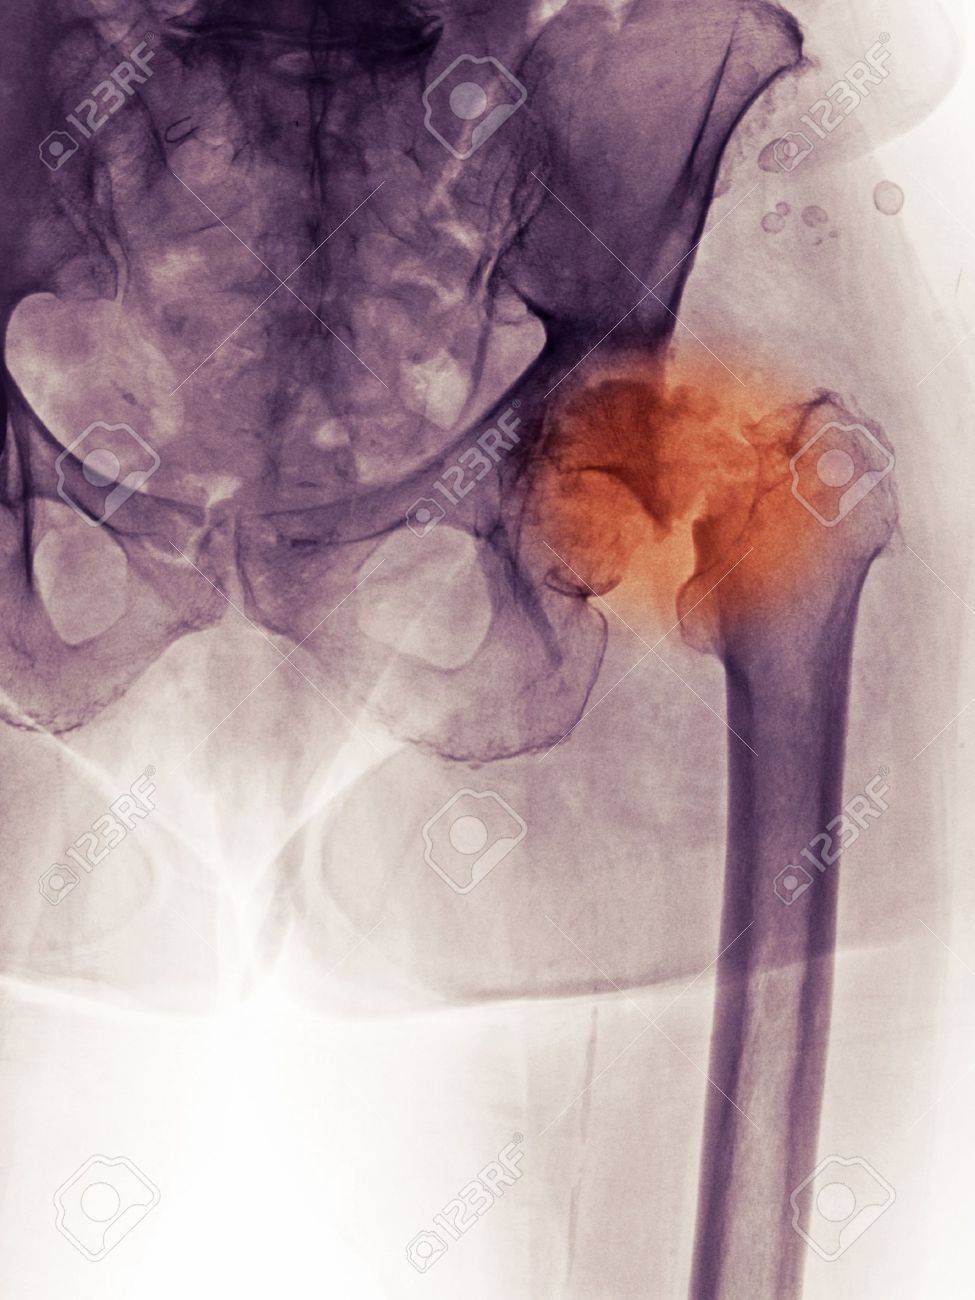

Der Hüftgelenksersatz ist eine der erfolgreichsten Operationen in der Geschichte der Orthopädie. Bei korrekter Indikationsstellung und Durchführung sind Erfolgsraten von weit über 95 zu erwarten sowie bei einer weit überwiegenden Anzahl der operierten Patienten eine Haltbarkeit der Endoprothese von mehr als 15 Jahren. Im Leben des Menschen wechseln Yin und Yang Phasen immer wieder ab.

Ob wir wollen oder nicht wir sind immer den Wellen zwischen Aktivität und Passivität weiblich - männlich Tag und Nacht und vielen anderen dieser Gegensätze ausgesetzt. Eine Versteifung der Hüfte sollte nur dann in Erwägung gezogen werden wenn eine Hüftprothese nicht möglich ist. Wiederkehrende Infektionen der Hüfte oder des künstlichen Hüftgelenks.

Alternativen wie Versteifung Gelenks-Amputation ergeben ein sehr unbefriedigendes Ergebnis für die Beweglichkeit und Lebensqualität des Patienten. Diese Prozeduren waren vor Jahrzehnten. Ganzes Bett schräg stellen oder erkrankte Extremität auf Schiene lagern.